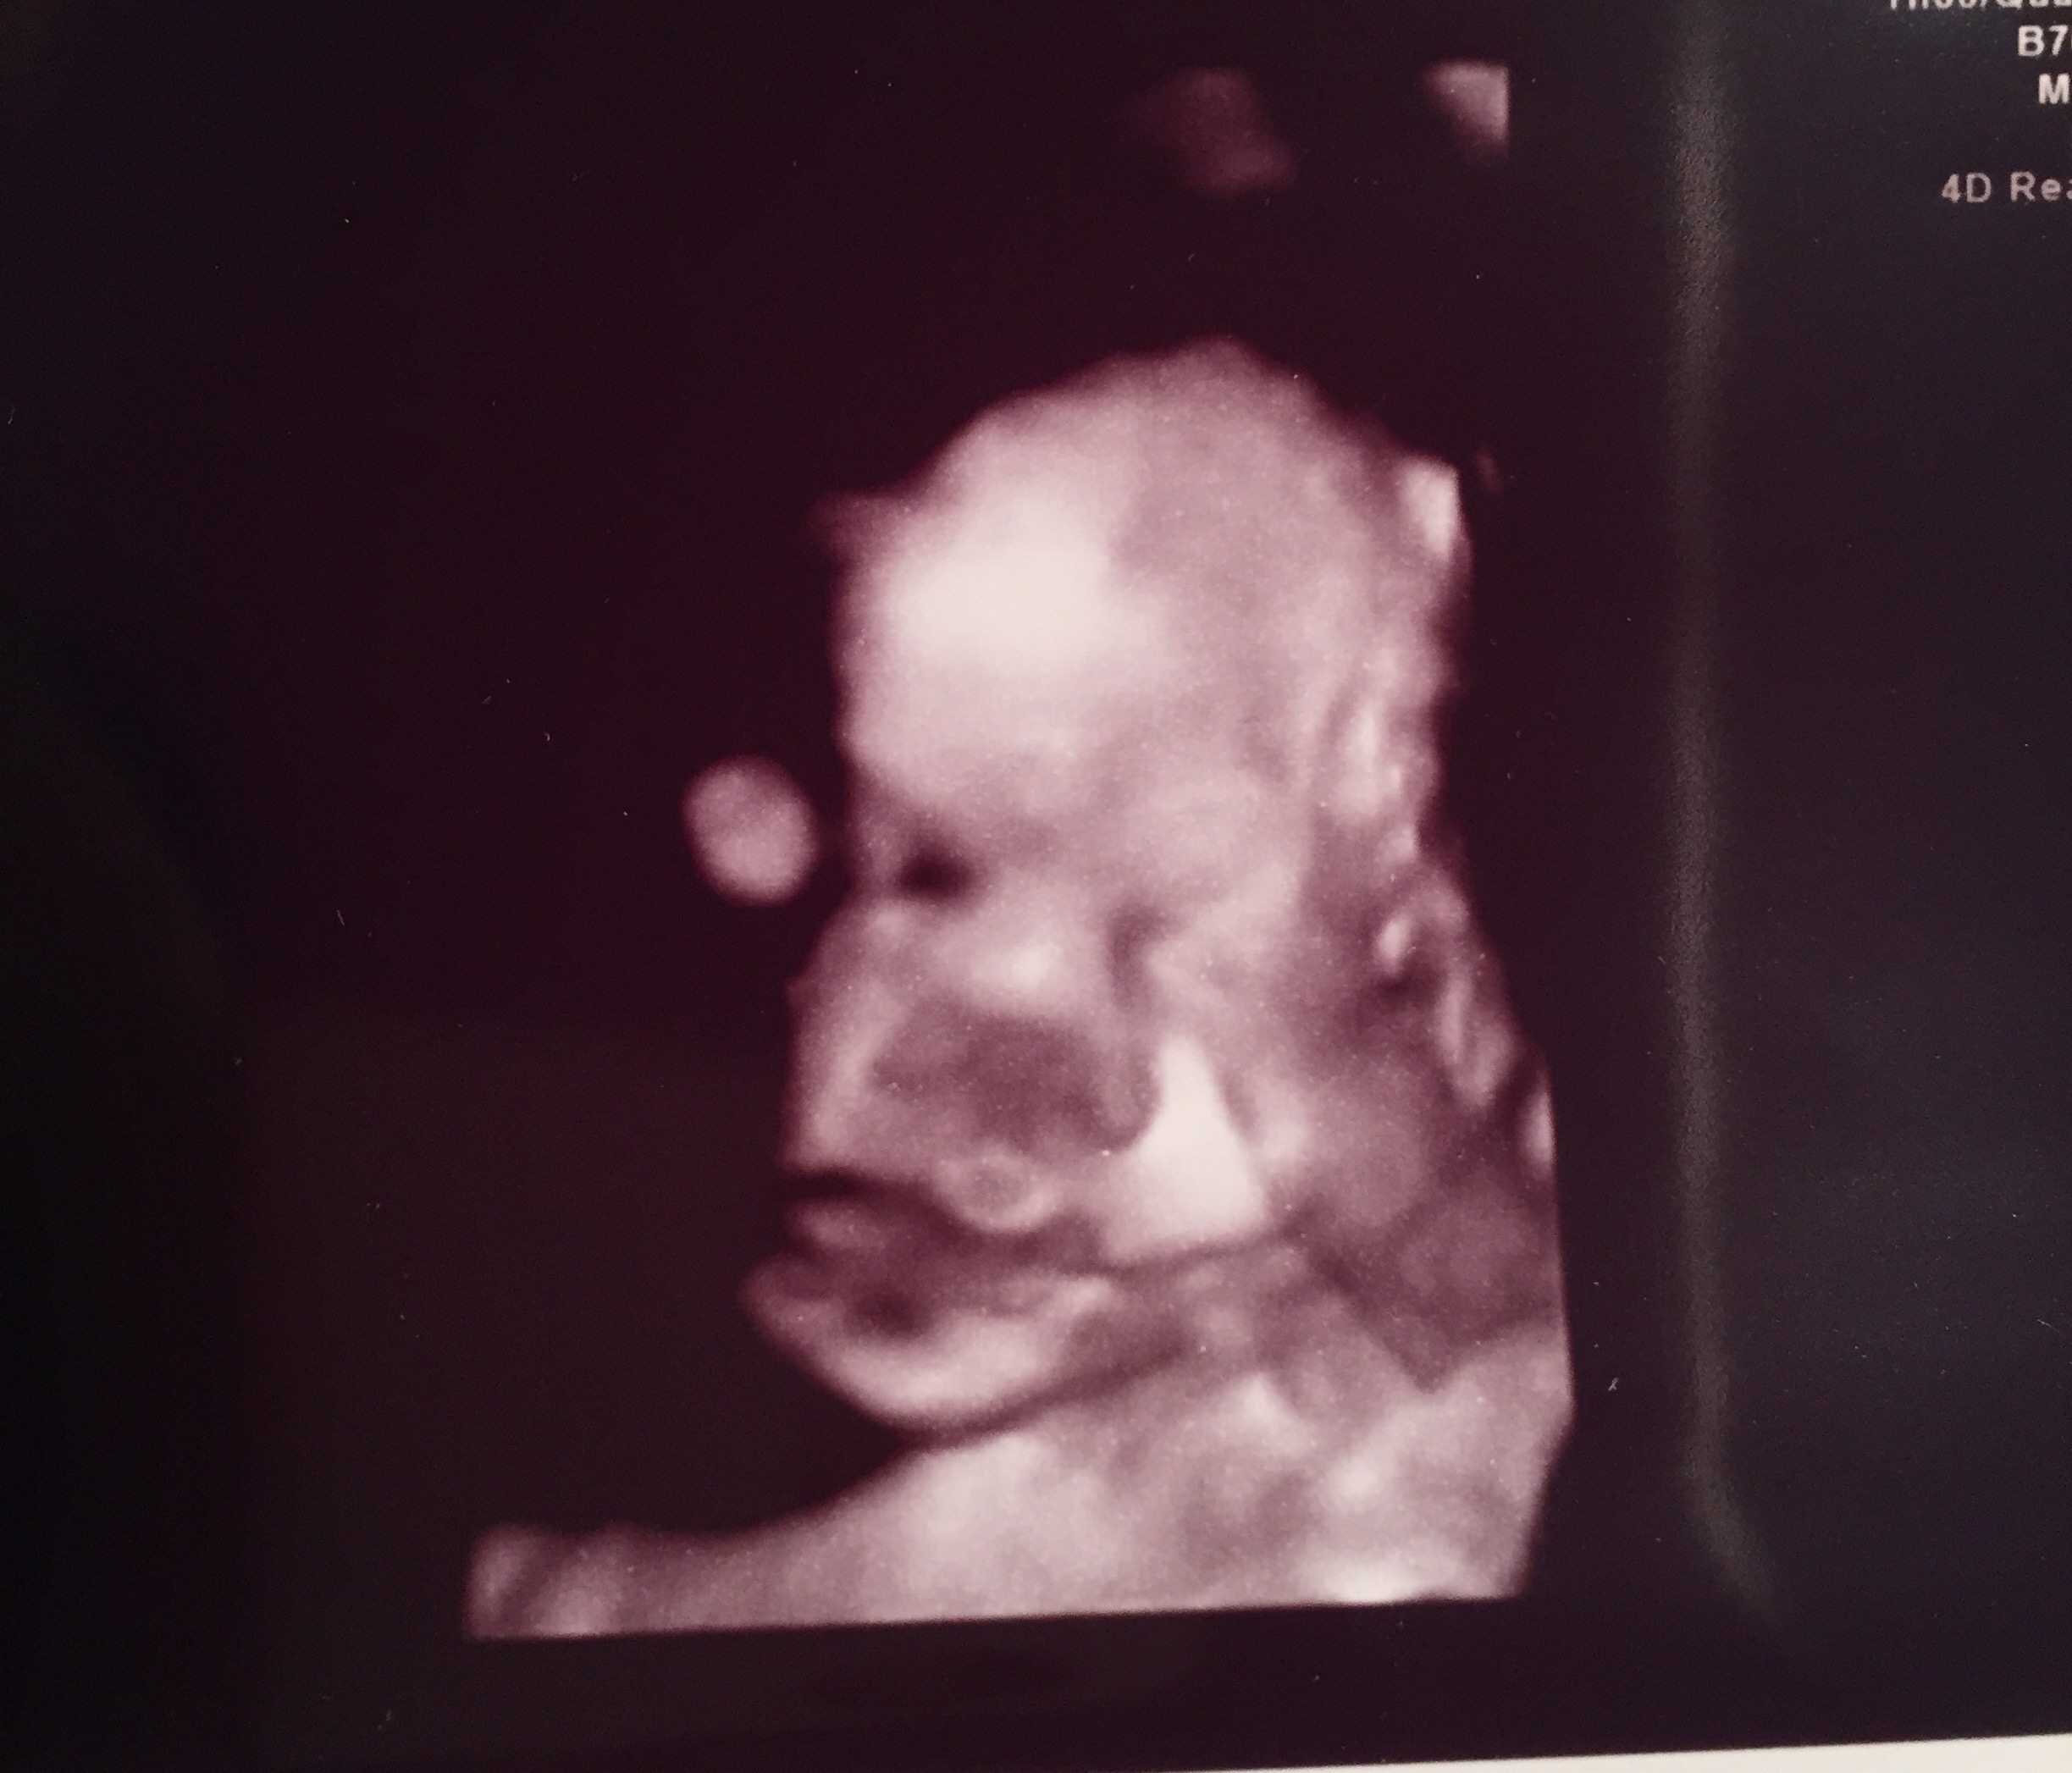

Skönt i alla fall att ha det överstöka och att höra att allt såg bra ut. Nu kan jag andas ut lite igen. Vi fick bild på vår lille. Häftigt med 3:d bilder, även om de ser himla roliga ut. Proportionerna är ju inte helt som i verkligheten och alla bulor och skuggor får bebisen att se ut som en liten potatis haha Men sjukt häftigt att se! Hon sa att han låg helt mosad med huvudet i bäckenet och att de inte var så lätt att få till en bild så här långt gånget men hon lyckades få fram halva ansiktet i alla fall. För övrigt låg han helt rätt och förhoppningsvis ligger han kvar så till förlossningen.

Vilken liten plutt 🙂